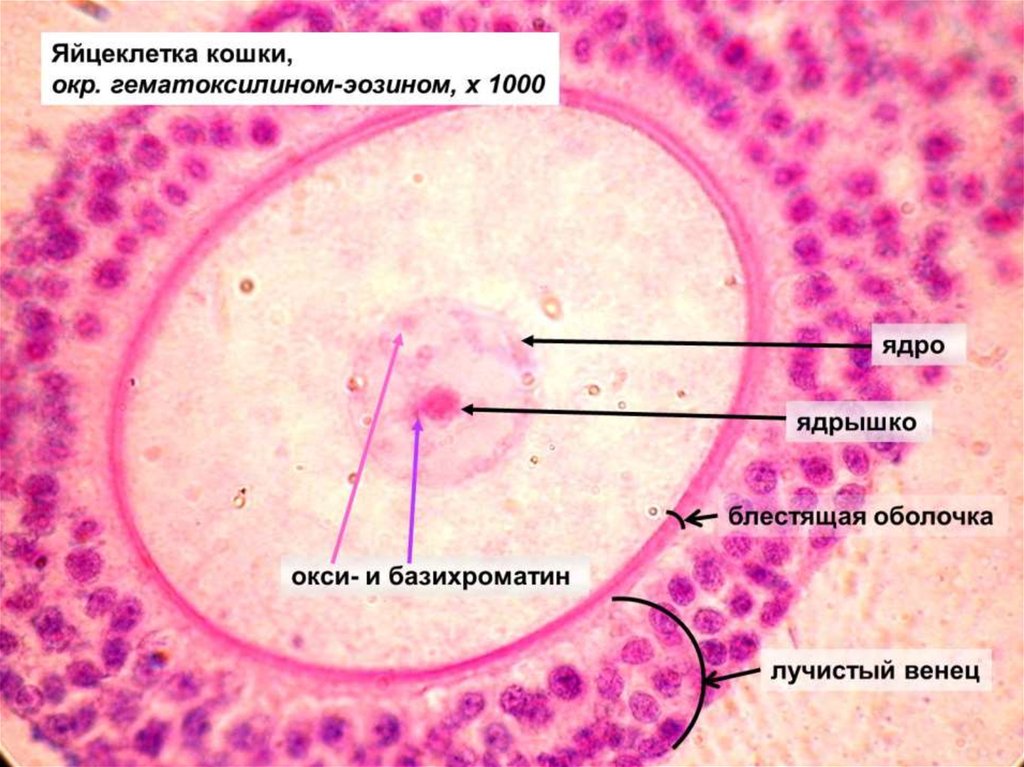

Созревание фолликула в яичнике: этапы и процессы

Раздел: Другие животные